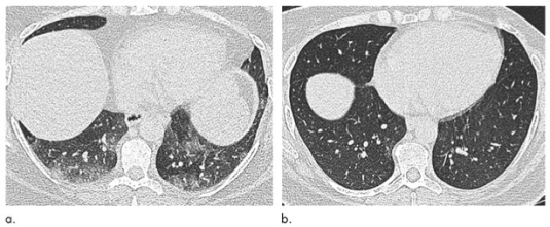

图2 与图1相同的51岁女性肺部轴位呼气末期CT图像,(a)减肥手术前和(b)体重减轻31 kg(体重指数降低31.6%)后6个月,术前患者出现了空气储留,但在手术后消失。请注意,由于膈肌偏移的差异以及由于肥胖引起的肺外限制增加对肺实质的影响,因此手术前后各部分的解剖位置会有所不同。